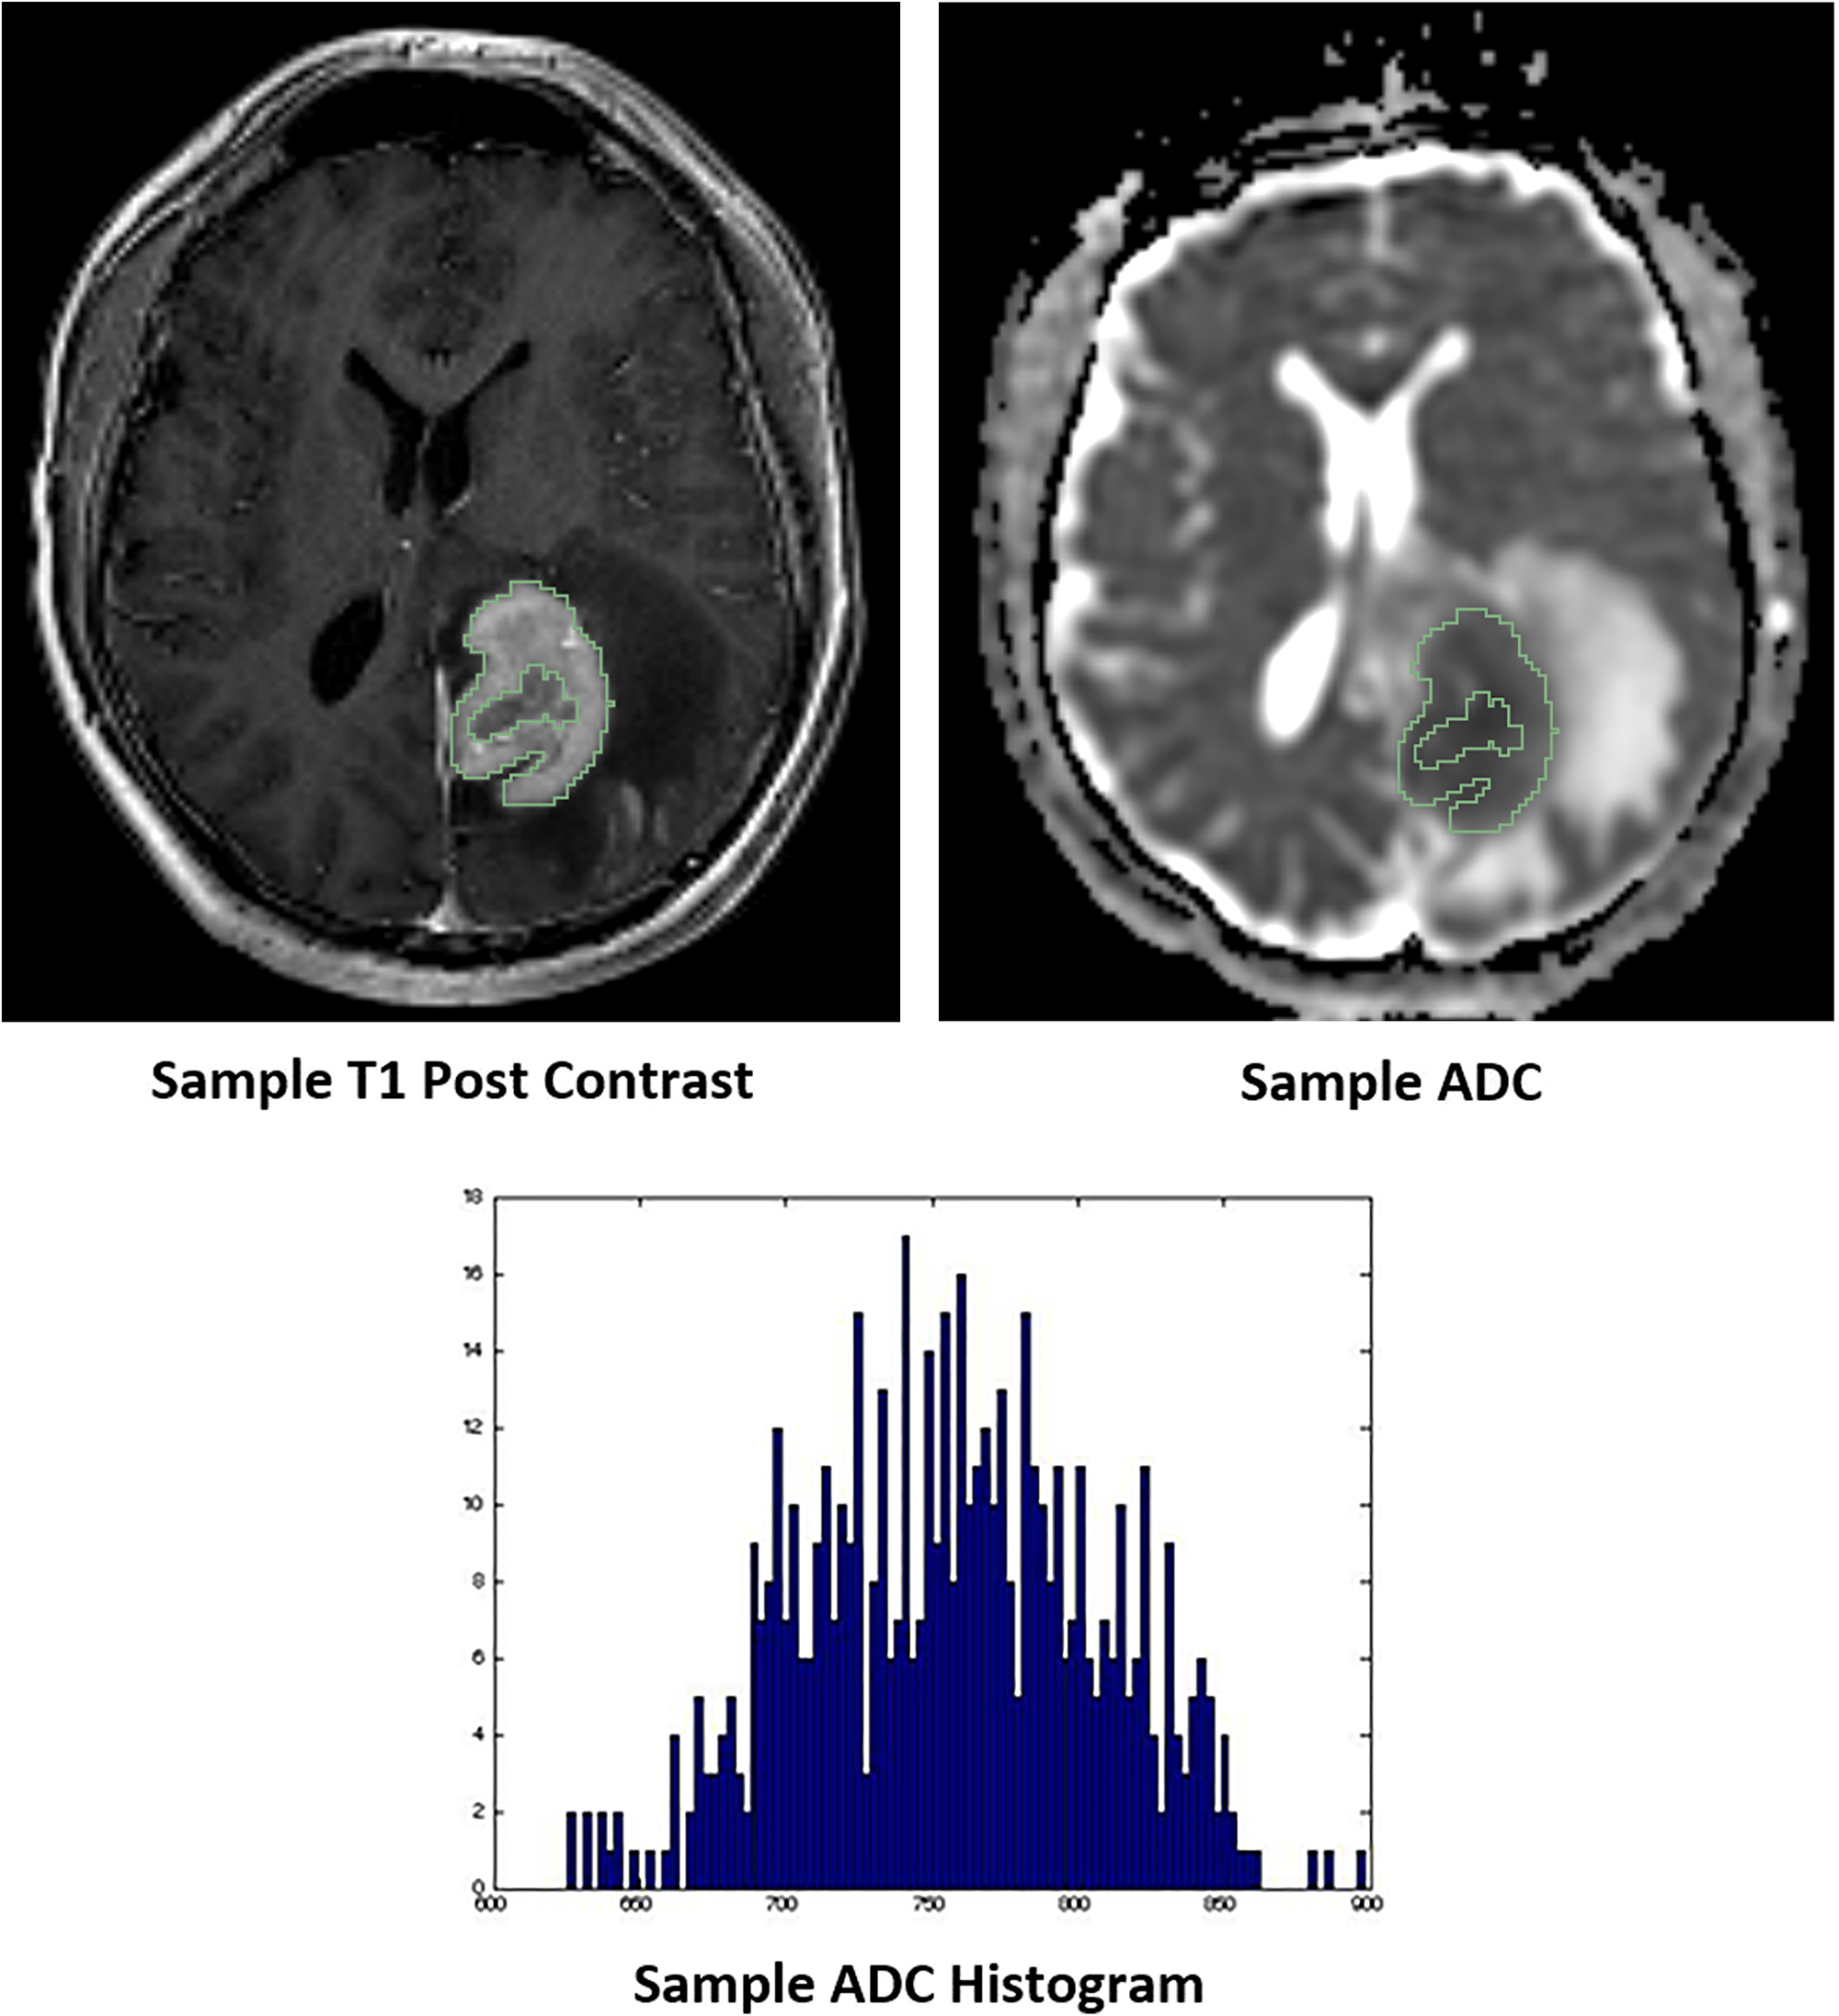

The cover for issue 45 of Oncotarget features Figure 3, "Representative images of whole tumor volume segmentation of the co-registered T1 post-contrast sequence and apparent diffusion coefficient (ADC) map, yielding the corresponding ADC histogram distribution utilized for data analysis," recently published in “Diffusion-weighted MR imaging histogram analysis in HIV positive and negative patients with primary central nervous system lymphoma as a predictor of outcome and tumor proliferation” by Khan, et al.

Figure 3: Representative images of whole tumor volume segmentation of the co-registered T1 post-contrast sequence and apparent diffusion coefficient (ADC) map, yielding the corresponding ADC histogram distribution utilized for data analysis.

However, tumor segmentation was performed using only the ADC sequence with the potential inclusion of intra-tumoral necrosis, hemorrhage or regions outside of the actual solid tumor that would otherwise have been excluded with contrast co-registration, ultimately providing a suboptimal representation of true tumor parenchyma.

The primary aim of this study is to more comprehensively evaluate the relationship between ADC calculations with tumor Ki-67 expression and clinical outcomes using a larger patient sample with the inclusion of PLWH and whole tumor segmentation with T1 post contrast co-registration.